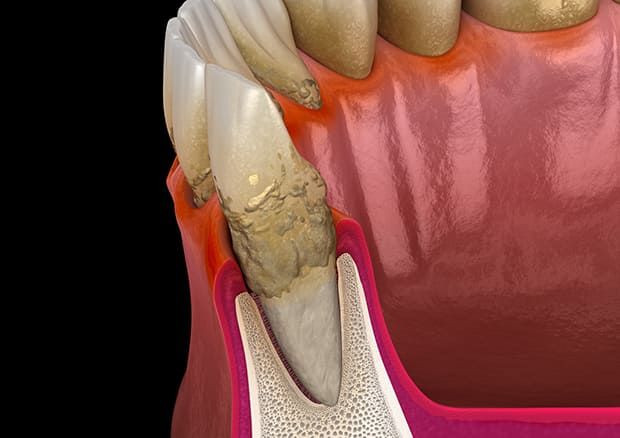

SRPとは、スケーリング+ルートプレーニングのことです。

このSRPは歯周病治療の1つで、専用の器具や、超音波の器具を用いて歯周ポケットの中、いわゆる歯茎の中の歯の根に隠れている部分の歯垢や歯石を取り除くことです。この歯石を歯肉の縁の下につく歯石ということから、縁下歯石(えんかしせき)といいます。

縁下歯石は、図のように黒っぽい色でセメント質と同一化し強固に付着しています。

当院のSRPは、特殊な医療機器を導入することで、迅速かつ合理的に縁下歯石を除去し、歯根表面を滑沢に仕上げることによって患者様の負担を減らし、治癒効果、歯周病再発予防効果に努めています。